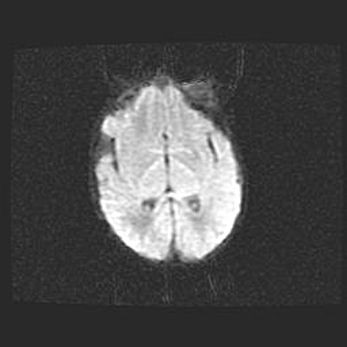

Церебральная ишемия II.

Возраст: 7 дней

Вес: 3350 г

Пол: женский

Окружность головы: 35 см

Срок гестации: 39 недель

Ишемия головного мозга – это состояние, которое развивается в ответ на кислородное голодание вследствие недостаточного мозгового кровообращения. У новорожденных она является следствием дефицита кислорода, что ведет к метаболическим расстройствам различной степени тяжести в тканях головного мозга, в том числе к развитию коагуляционных некрозов и гибели нейронов.